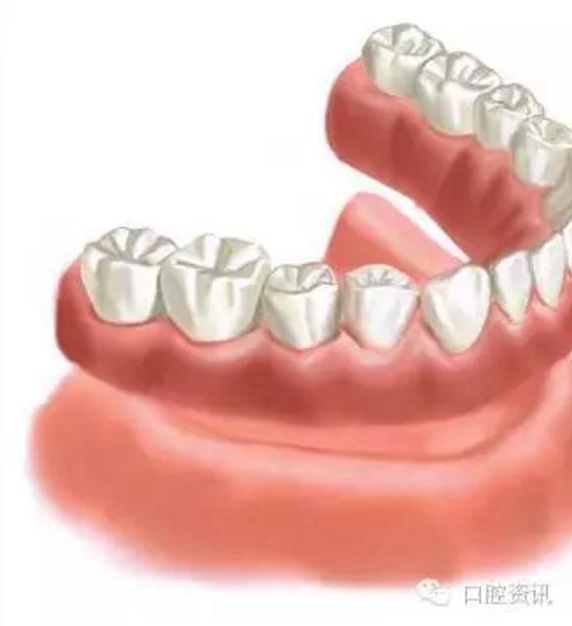

4 . 全口義齒

傳統(tǒng)的全口義齒利用牙床和黏膜提供固位力。而當(dāng)天然牙缺失后, 牙槽骨會逐漸吸收, 這會影響義齒的穩(wěn)定度, 進(jìn)一步會影響您的咀嚼功能和舒適感。義齒可能需要反復(fù)調(diào)改才能達(dá)到滿意的效果。這種情形下, 通過種植體支持全口義齒, 可以有效地提高義齒的固位力。

9.jpg

圖9. 傳統(tǒng)的全口義齒 (活動假牙)